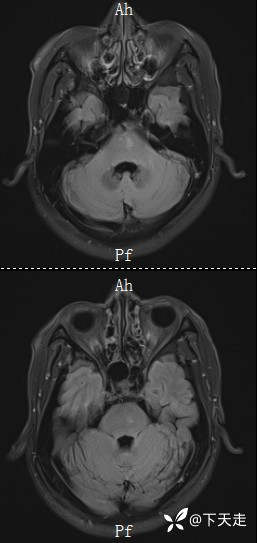

住院治疗第8天,夜间3点上厕所时感觉右侧肢体无力加重,未在意,继续卧床休息,7点肢体无力加重明显,右侧上下肢不能抬举,右侧下上肢2级。立即复查CT,排除脑出血,复查磁共振如下